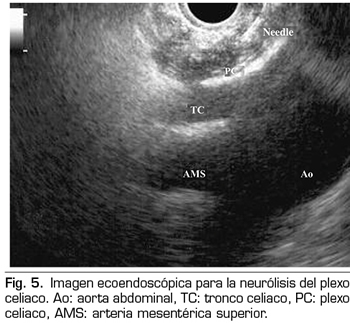

Se realiza mediante un abordaje posterior retrocrural, normalmente guiado por fluoroscopia (Figura 6). Las lesiones pueden llevarse a cabo mediante radiofrecuencia convencional o utilizando agentes neurolíticos como en el plexo celiaco.

Técnica percutánea